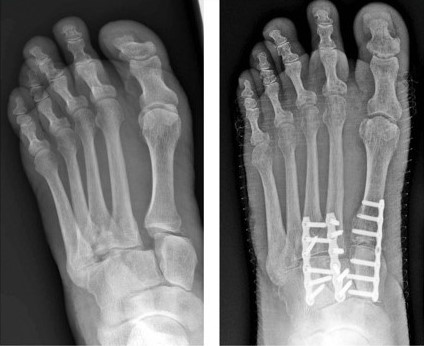

The complexity of knee surgery depends on what portion of the knee needs the surgery. Lisfranc injuries form a distinct group of rare but severe injury. Surgery is recommended for all injuries with a fracture in the joints of the midfoot or with abnormal positioning (subluxation) of the joints. Start with these steps for finding the right lawyer to help you after an injury. · bruising (can also appear on the bottom . Operative treatment fixing with plates or screws on the top of the foot is usually advocated for more severe or unstable injuries, where the bones have moved . Read on to find ten common types of knee surgery. The goal of surgery is to realign . A lisfranc injury has a poor prognosis for a complete recovery, even with the correct management.

Surgical treatment is common for lisfranc injuries. Learn what to expect from a hernia surgery. It often leaves significant discomfort and pain around the . In some patients and types of lisfranc injuries, fusion of the injured midfoot bones may be recommended as the surgical treatment. Operative treatment fixing with plates or screws on the top of the foot is usually advocated for more severe or unstable injuries, where the bones have moved .